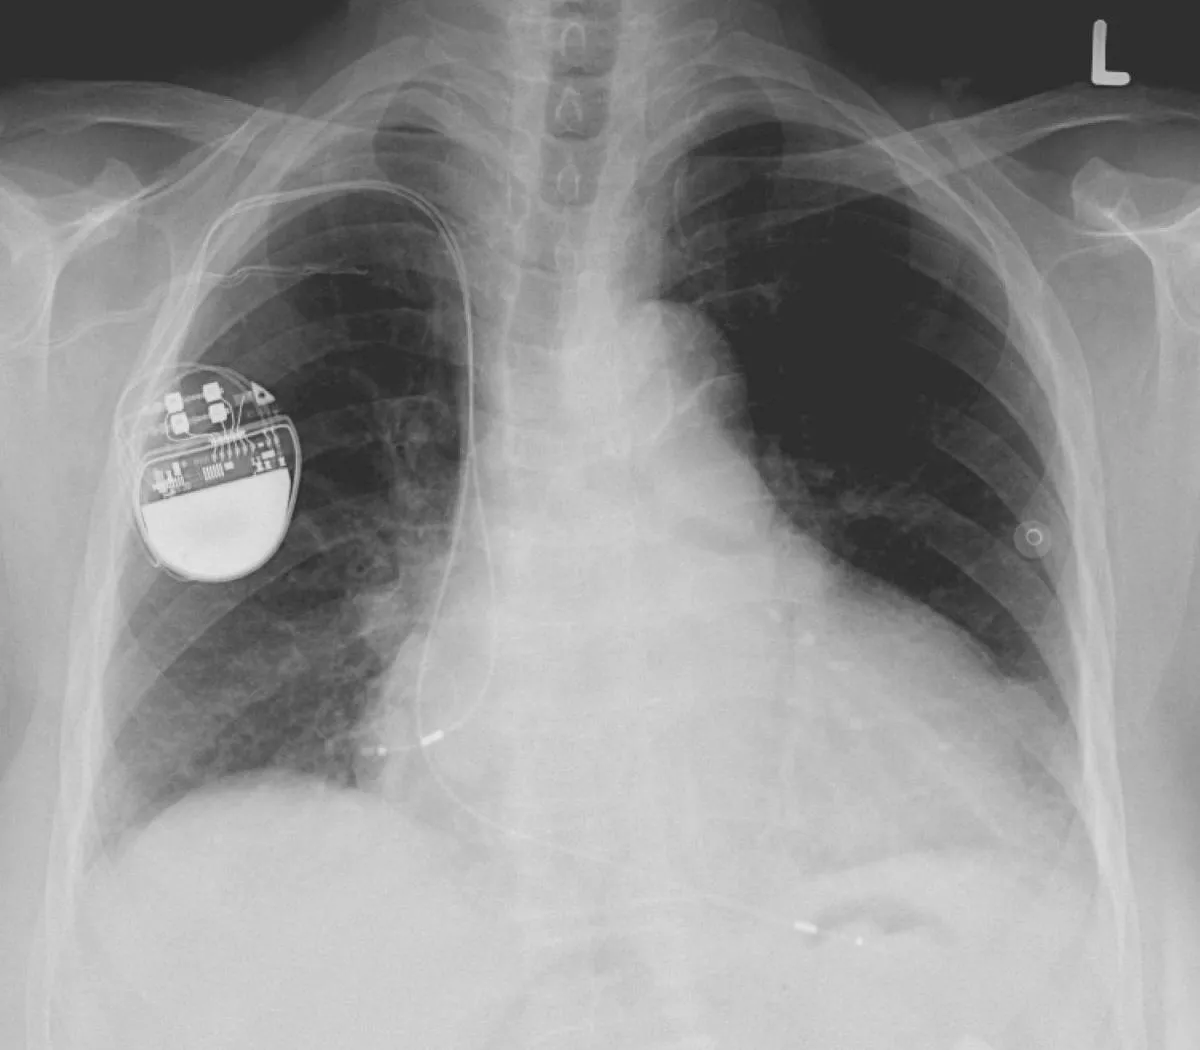

Beültetett pacemaker (szívritmus-szabályozó készülék) mellkasi röntgenfelvételen.

Lucien Monfils; liszensz: CC-BY-SA (Wikimedia Commons)